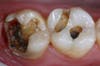

Mercury (as in a thermometer) expands and contracts with change in temperature, every time you consume anything hot or cold. This amalgam filling is sitting in a tooth that resembles glass or china. This chunk of metal then expands and contracts within this brittle tooth. So what do you think it will do to the tooth surrounding this material? That’s right, it will cause fractures. Fractures can break the tooth. How many of you have had a crown because your tooth broke but the filling was still intact?! Fractures also will leak, allowing bacteria to penetrate within, causing decay (cavities). The photos I have posted to this blog clearly show what we see when we remove the amalgam.